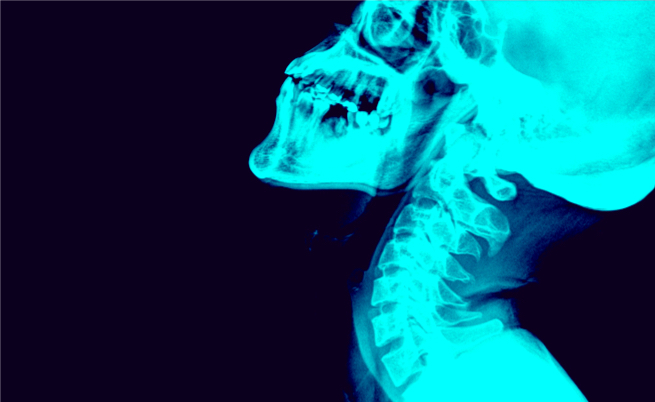

Come sappiamo, la risonanza magnetica è un esame medico che utilizza campi magnetici e onde radio per ottenere immagini dettagliate dell’interno del nostro corpo. A differenza dei raggi X e delle scansioni TC, non espone i pazienti alle radiazioni ionizzanti.

Questo tipo di test non prevede l’uso né di sostanze radioattive né di radiazioni ionizzanti. Per fornire immagini dettagliate sfrutta, invece, onde a radiofrequenza e potenti magneti che creano campi magnetici di alta intensità.